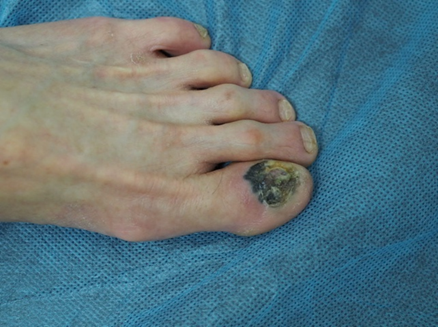

但要是突然有一天,皮肤长了一些莫名其妙的东西出来,比如突然变大变奇怪的黑坨坨,大家一定要有警觉性!

图片来源:医生提供

这可能是皮肤癌中最可怕的恶性黑色素瘤